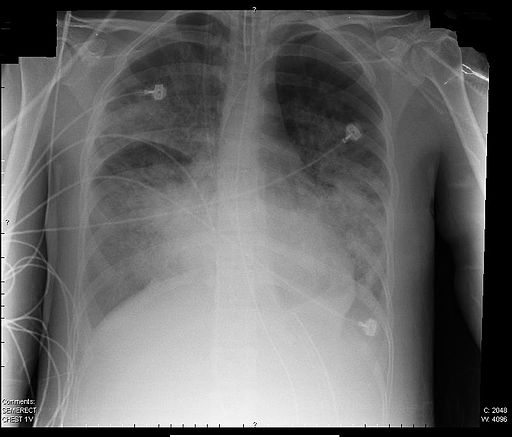

Acute respiratory distress syndrome, ARDS, is a final pathway for many infectious and traumatic events. The response of the lungs, in this case, to coronavirus, is to summon the immunologic cavalry. The immunologic response unintentionally thickens those alveolar membranes, making it more difficult for oxygen to diffuse. The inability to deliver oxygen from the bloodstream to our organs will subsequently cause them to fail over time, tightening the death spiral. [1]

The thickening of the alveoli makes the lung stiffer, creating more work for our respiratory muscles to expand the lung during inhalation; and reducing the elastic recoil of the lungs that expels air with exhalation. These two effects cause the tidal volume to fall. The rate of breathing increases to compensate, but the muscles already under additional stress, tire; you cannot breathe rapidly, termed tachypnea, for long periods. Mechanical ventilation seeks to restore adequate oxygenation